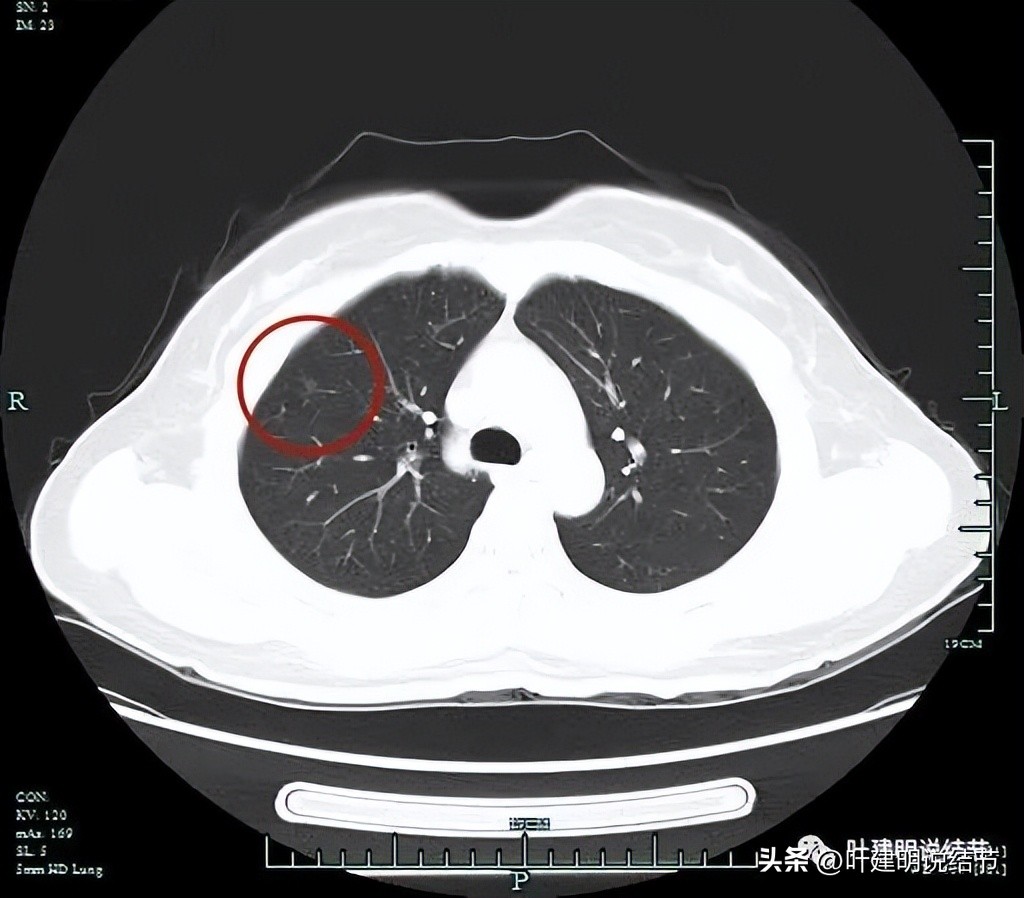

非薄层图像:

病灶1:右上叶淡磨玻璃结节,边缘较糊,似有微小血管走向病灶。

病灶2:右上叶混合磨玻璃结节,边缘毛糙,中间有空泡征,邻近有微小血管走向病灶。

病灶3:右下叶近叶裂处微小磨玻璃结节,偏长条状,有微血管进入。